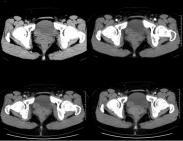

長骨骨干結核(tuberculosis of long bone shaft)很少見,其發病順序為股骨、脛骨、橈尺骨干、肱骨干和腓骨干。10歲以下的兒童最多,且常為多發。30歲以上的則很少見。